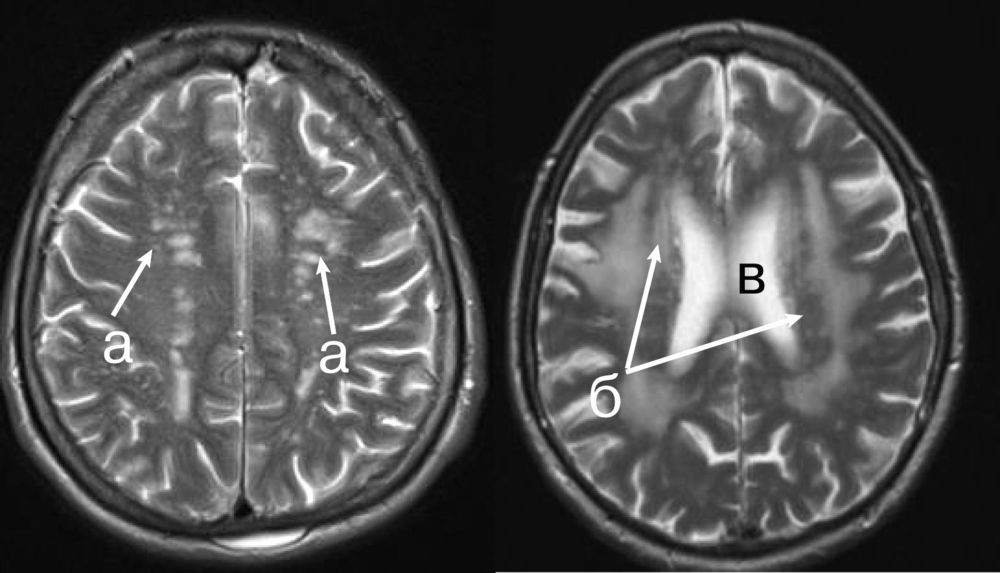

Демиелинизирующие заболевания мозга: МРТ изображения